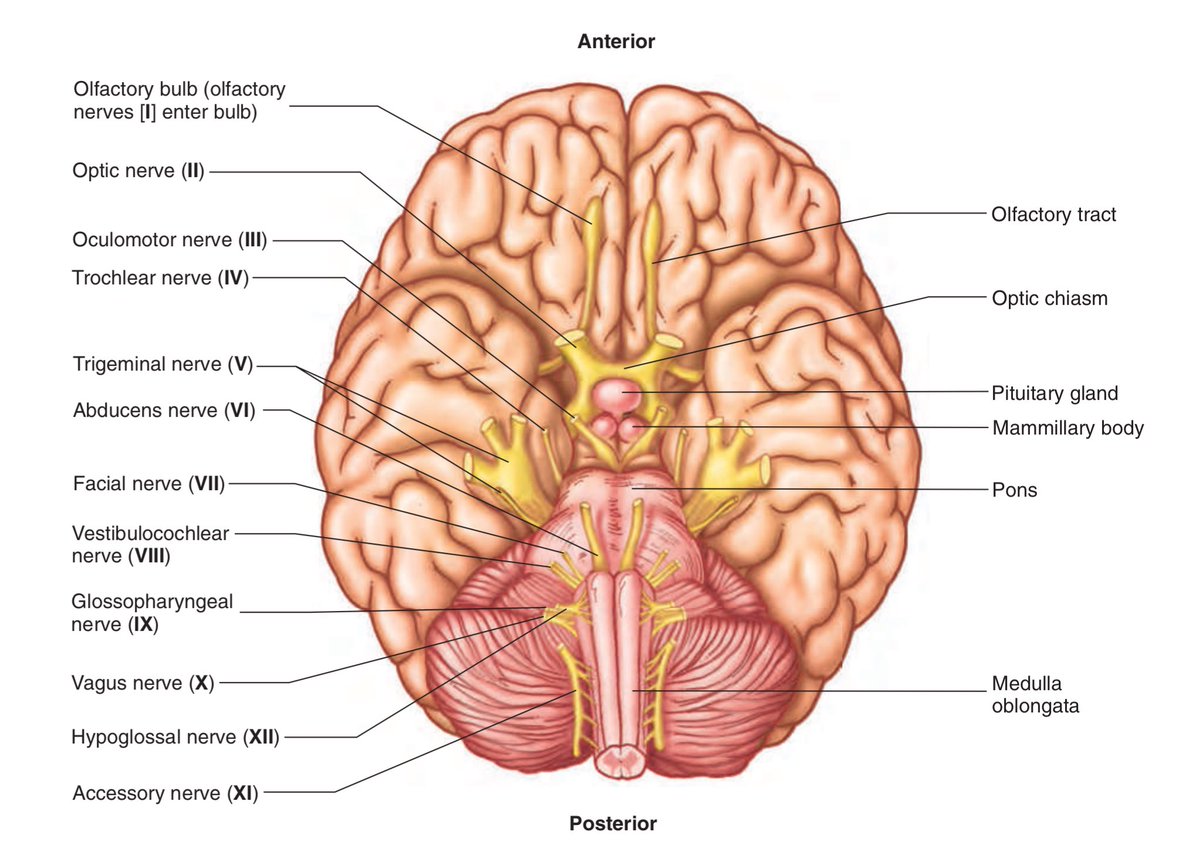

実はこの構造は脳軟部組織の構造に対応したもので、それは下の画像を見ると良く分かる。

Twitter より

これらの画像は全て顔面が上、後頭部が下になっており、まず中心の溝によって脳が左右二つの半球に分けられ、それぞれが前頭葉、側頭葉、小脳(背後に後頭葉)の三つに分けられる事によってほぼ六等分に近い形になっている。

イメージとしては6Pチーズのデザインを思い浮かべたらよいだろう。ほぼ六等分に区切られた脳軟部組織にフィットする様に、まるで区切りのあるステンレスのインドカレー皿みたいに、頭蓋底に六つの仕切りが出来ているのだ。

二枚の画像を重ねると、頭蓋底中央付近に空いている大きな穴は、太いロープ状の脳幹が脊髄となって首へと続くために出る穴だと分かる。